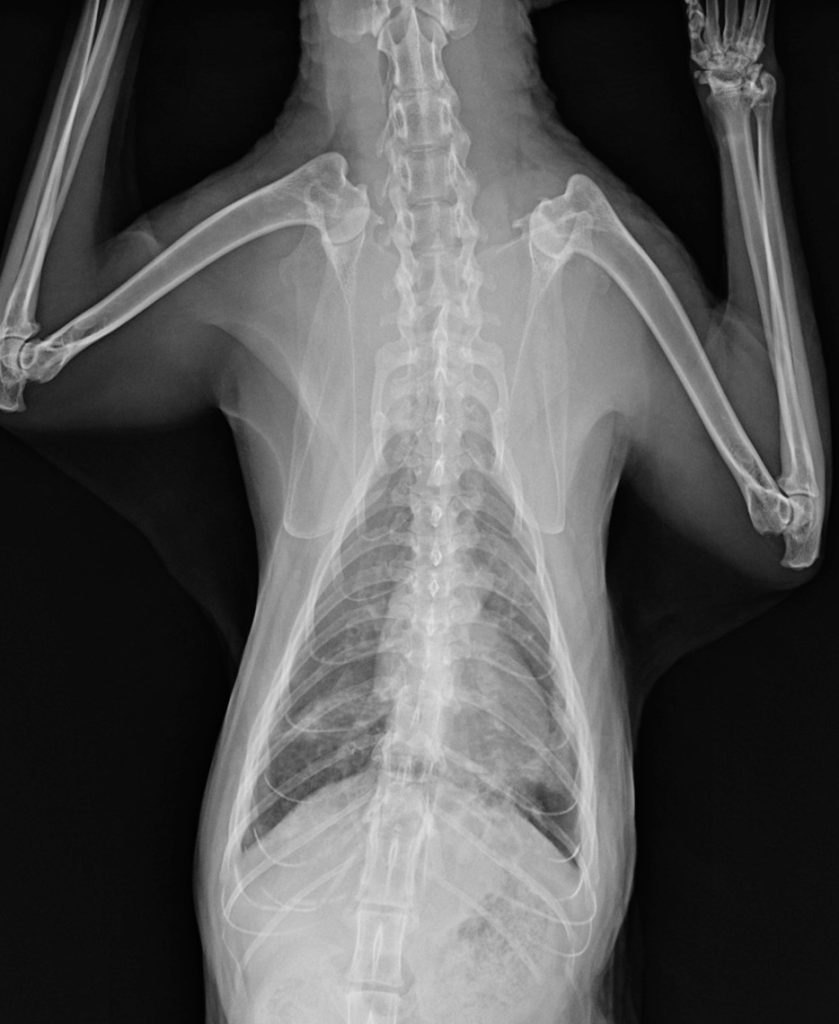

腫瘍や炎症の可能性を考えました。特に足や指の腫瘍も考えましたが、左右の前足で同時に症状が出ていることに違和感を感じました。足や指の腫瘍なら、通常は片方の足だけ出ることが多いです。そこで、ある疾患が鑑別疾患に挙がり、肺のレントゲンを撮影しました。

この結果からやはり鑑別疾患に挙げていた肺指(はいゆび)症候群と診断しました。肺指症候群とは、肺癌が四肢の指先に転移する猫ちゃん特有の病態です。

また、診断時には肺癌が指以外にも全身転移していることがほとんどで、予後は極めて悪く、余命は1-2ヵ月程と言われています。肺癌でも末期的な状態なので積極的な治療は難しく、今回は痛みを取ることが中心の緩和治療を実施することになりました。